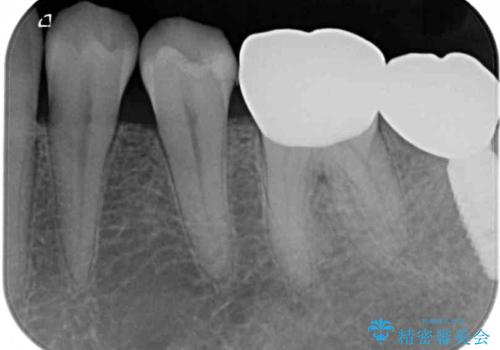

- 左下の歯が欠けてしまったとのことで来院された患者様です。

大きな銀歯が装着されており、その周りからむし歯が広がっている状態でした。

特に症状はなく、神経組織も健全な状態であったため、むし歯を全て取り切った後にフルジルコニアクラウンにて補綴することとしました。